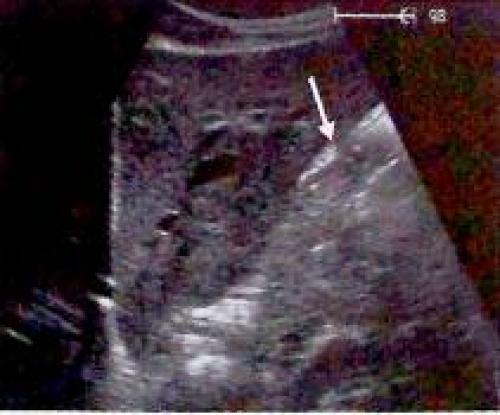

Ультрасонография желудка

При ультразвуковом обследовании желудок и двенадцатиперстная кишка чаще всего рассматриваются в виде структур, затрудняющих визуализацию других органов. Лишь изредка осуществляется их целенаправленный поиск и обследование. Данное обстоятельство, пожалуй, можно объяснить тем, что желудок и двенадцатиперстную кишку никак нельзя отнести к классическим органам для ультразвукового исследования, хотя у подготовленного пациента они просматриваются не так уж и плохо, да еще, если и врач знает, на что именно направлен его поиск. И все-таки следует отметить, что ультразвуковое исследование желудка и двенадцатиперстной кишки под силу только опытному специалисту.

Далеко не всегда удается выделить пять слоев стенки желудка. Как правило, лучше всего виден срез антрального отдела желудка, зачастую же видны только три слоя: гиперэхогенные внутренний и наружный слои и гипоэхогенный средний слой. Датчик располагают в верхнем левом квадранте живота. У пациентов натощак слои стенки антрального отдела желудка могут быть видны позади печени и непосредственно перед поджелудочной железой. Тень от воздушного пузыря мешает адекватному обследованию пациентов с метеоризмом или после приема пищи. Если желудок значительно растянут, необходимо искать опухоли стенки или утолщение стенки как проявление гипертрофии пилорического отдела. В зависимости от степени сокращения, стенка желудка должна иметь толщину 5—7 мм, и гипоэхогенный мышечный слой в ней не должен превышать 5 мм. Любые подозрения на поражение стенки желудка следует разрешить последующей гастроскопией или рентгенографией.

Для точной оценки слоев стенок желудка его заполняют 500 1000 мл чая или воды (заглатывается через соломинку). При необходимости внутривенно может быть введено 20 мл бутилскополамина (гиосцина бутилбромид).Используется датчик: 5,0 МГц. Датчик 3,5 МГц лучше использовать для обзорных снимков, в особенности для оценки задней стенки и дна желудка. Пациент обычно находится в положении лежа на спине, однако иногда используются специальные положения.

На аппарате с высокой разрешающей способностью и при благоприятных условиях обследования иногда удается выделить пять слоев стенки желудка (1):

- гиперэхогенная граница между полостью и слизистой оболочкой;

- гипоэхогенный мышечный слой слизистой оболочки;

- гиперэхогенная подслизистая оболочка;

- гипоэхогенная мышечная оболочка;

- гиперэхогенная наружная граница серозной оболочки.

Рис. 1. Послойное строение стенки желудка (^).